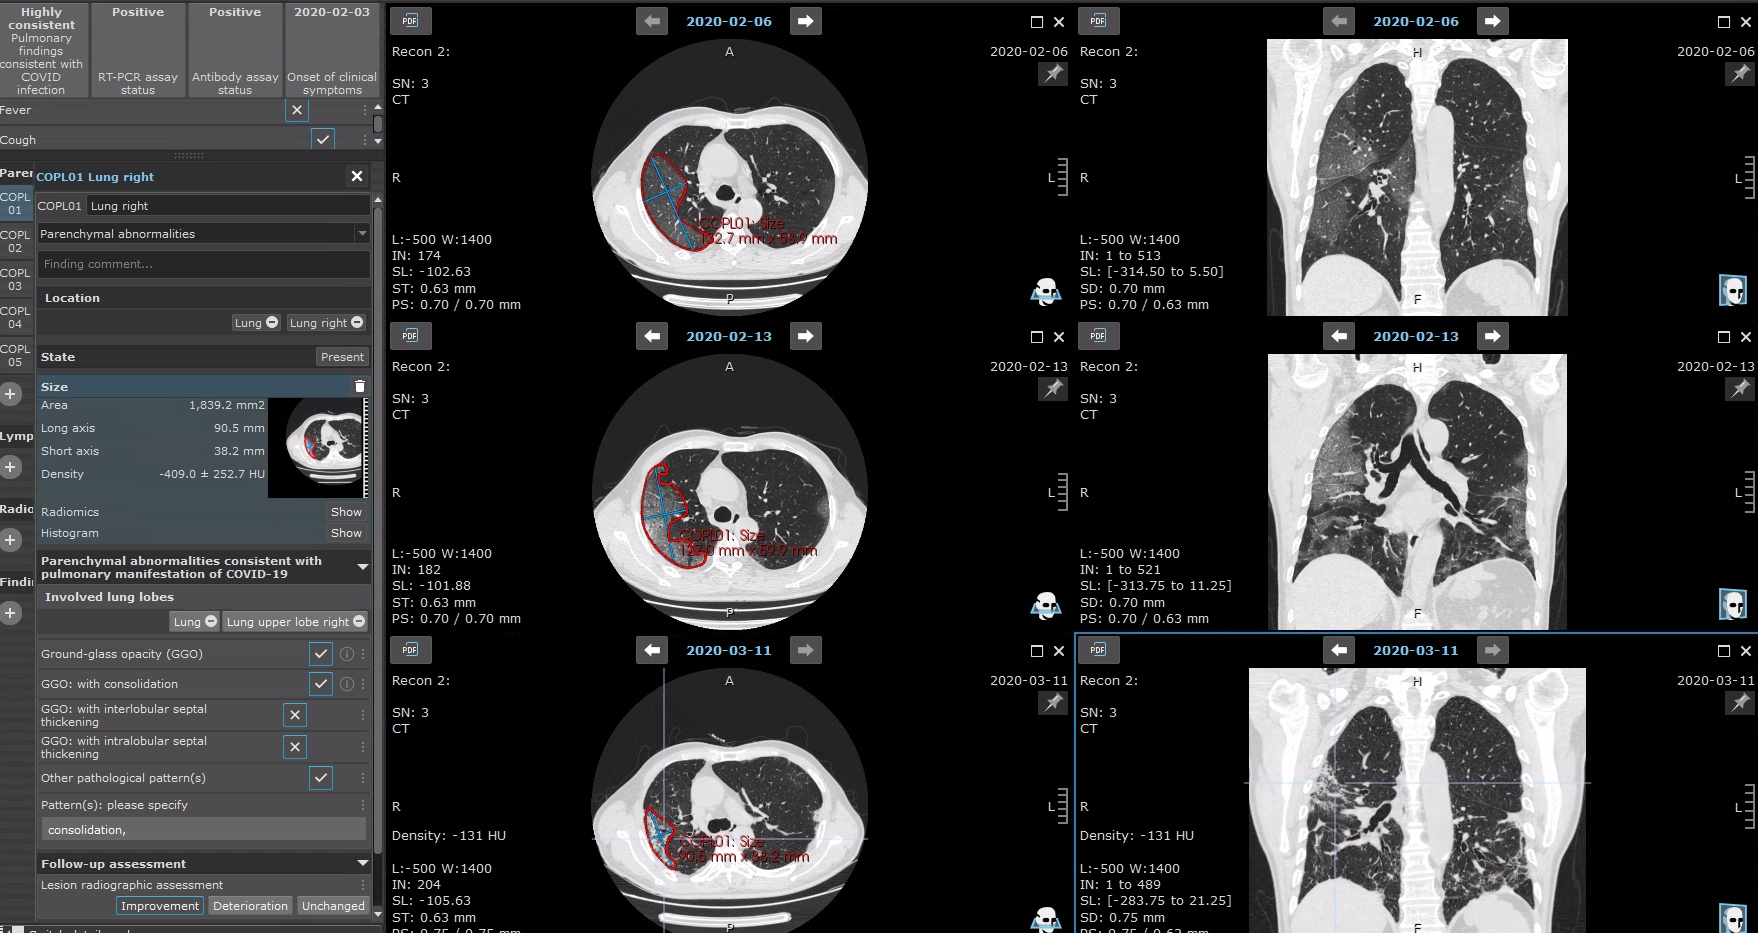

Based on the evidence available back in April 2020, the first version of a COVID-19 Mint EDC was drafted. It is based on the mint LesionTM medical software platform (Mint Medical GmbH, Heidelberg, Germany). Thereby, we enabled structured data annotation directly on primary imaging data from chest computed tomography. In addition, patient history and clinical data are reported in a standardized way in the evidence-based, context-assisted template. As an established software in radiological reporting, mint LesionTM and thus the developed COVID-19 EDC are able to depict disease courses and assess the progression of disease. In order to facilitate rapid, joint data acquisition early in the pandemic, we launched a cloud-based web platform for data to be uploaded, assessed, aggregated and analyzed.

Eight European medical centers including ExploreCOVID centers (BMBF 01KI2054) were willing to prove the feasibility of this concept. They uploaded data from 283 patients, who either had laboratory confirmed Sars-CoV-2 infection or suspected infection based on clinical presentation. Clinicians and radiologists were guided through the whole data annotation process by the tool. Automatic conformity checks of the annotated data and rule-based evaluation were used to improve reporting. A particular strength lies in the permanent linkage of structured imaging-based values including automatic radiomics features with clinical data. The automatic generation of reports for single time points or disease courses of individual patients provided standardized disease assessment according to best scientific knowledge at the time. The developed COVID-19 EDC can be dynamically adapted to new scientific developments without losing any previously collected data. It has continuously been updated and is currently in its third version. In Germany, this reporting concept was adapted and subjected to further development by the nation-wide research initiative RACOON (Radiological Cooperative Network) [https://www.netzwerk-universitaetsmedizin.de/projekte/racoon], in which all university hospitals are participating.